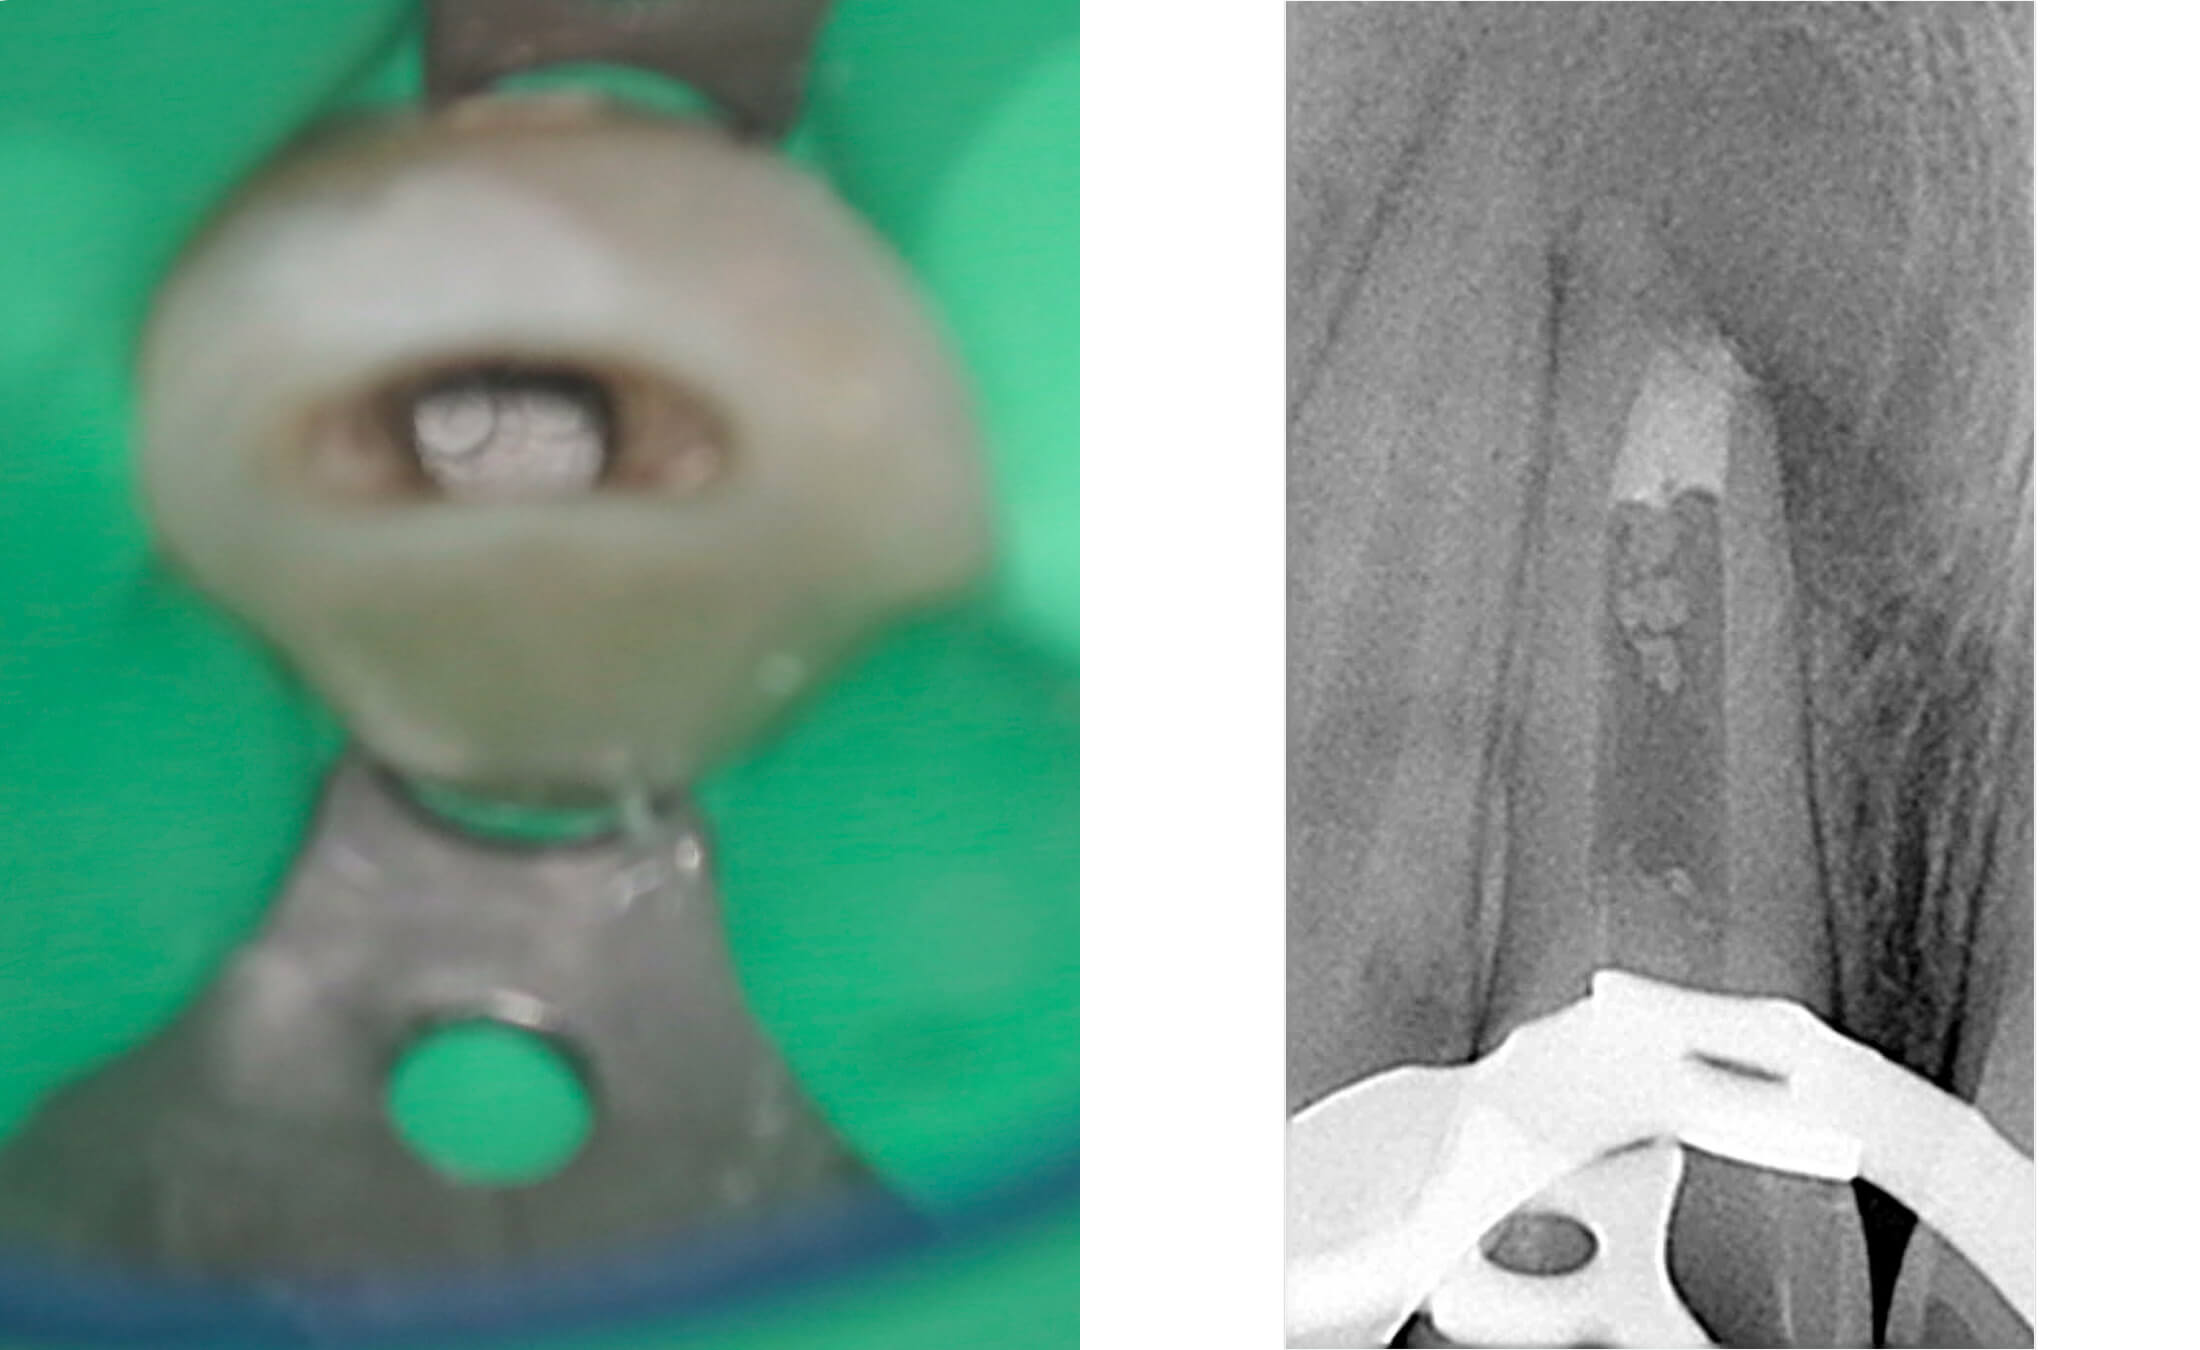

4. Во второе посещение сформирован апикальный барьей из МТА, просвет корневого канала обтурирован гуттаперчей с эпоксидным силером. (Фото 7-10)